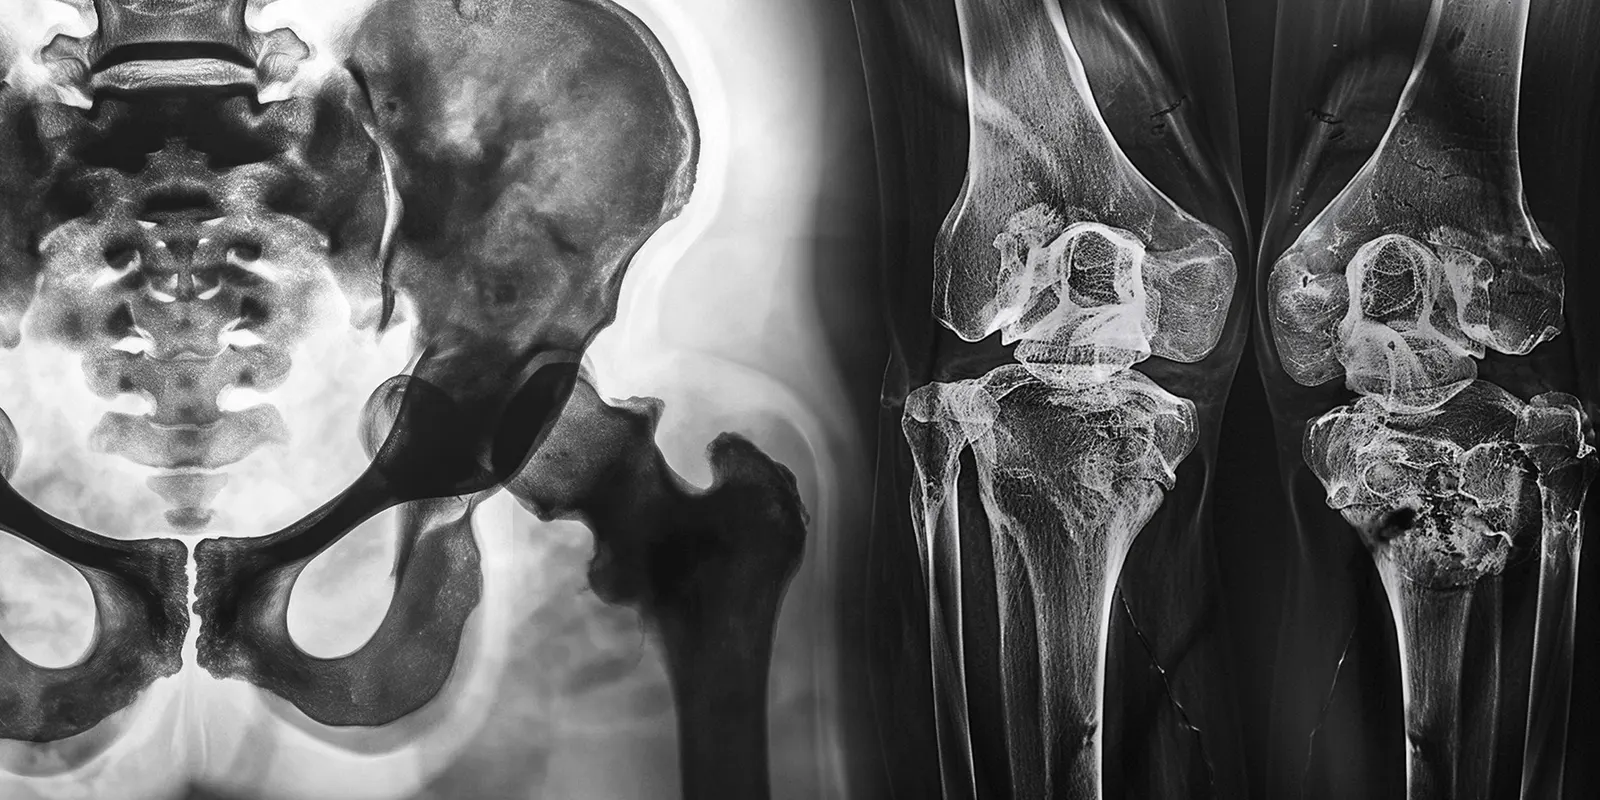

Gracias a un equipo de expertos detrás de cada intervención, el Dr. José Ignacio Sánchez logra resultados inigualables que aumentan la calidad de vida de todos sus pacientes. Asimismo, su especialidad en cirugía ortopédica y traumatología le permite proporcionar opciones efectivas para recuperar la funcionalidad de la cadera y rodilla.

Reemplazo de cadera

Con este procedimiento nos encargamos de reemplazar las partes de la articulación de la cadera dañadas, por implantes de alta calidad. Como traumatólogo en Bogotá el Dr. logra resultados de movilidad únicos.

Reemplazo de rodilla

Cuando los dolores en la rodilla son intensos y se presenta rigidez, la cirugía de reemplazo de rodilla es una alternativa adecuada. Incorporamos implantes artificiales para sustituir superficies óseas.